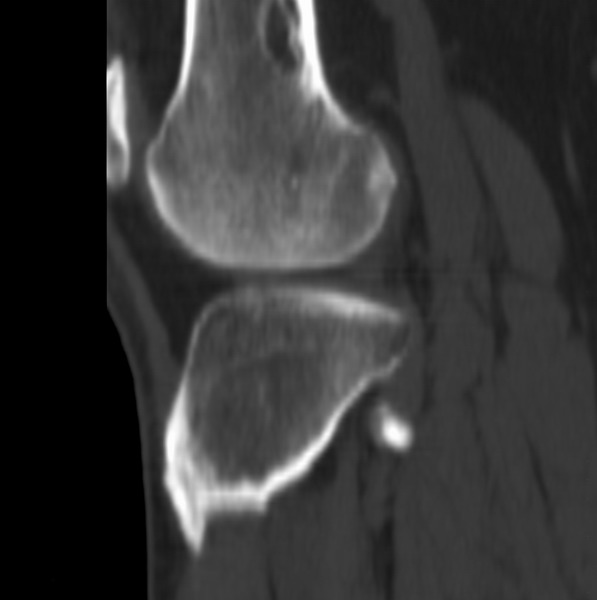

右侧膝关节疼痛一月

男、48

股骨下段、胫骨上段。

股骨干骺端病变考虑非骨化性纤维瘤。

支持非骨化性纤维瘤

非骨化性纤维瘤